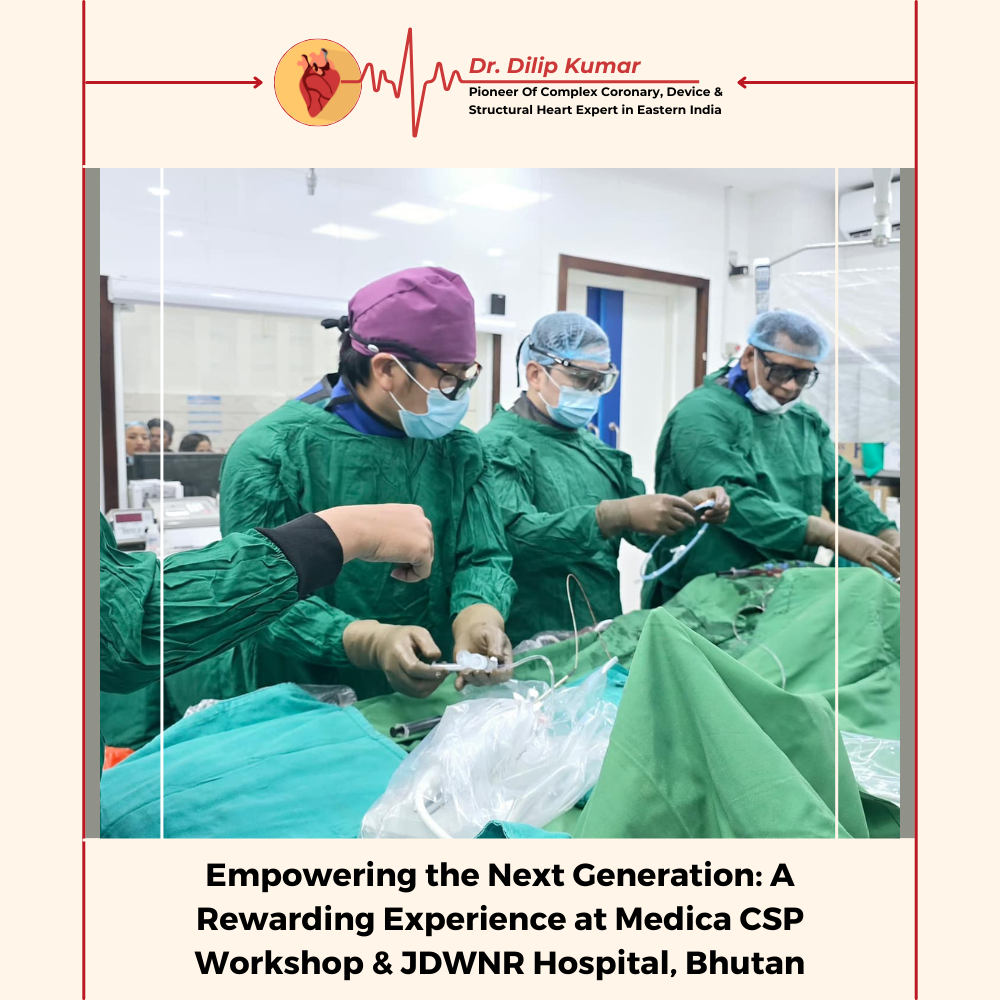

Mentoring young colleagues in their careers is truly rewarding. It was a pleasure to have enthusiastic young operators at our Medica CSP workshop. Additionally, I thoroughly enjoyed scrubbing with Dr. Mahesh at JDWNR Hospital in Thimphu, Bhutan.

"A Milestone in Cardiology: Successful CSP and CRT-D Procedures at JDWNRH"